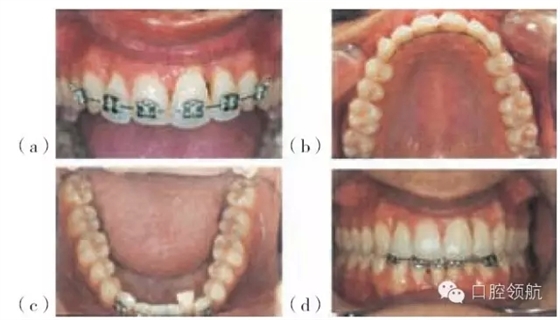

圖29.8 圖29.7患者正畸治療的過程:(a)上頜固定矯治器。(b)上頜腭側(cè)保持器。(c)下頜固定矯治器。(d)排齊(永久保持)的上頜前牙及下頜固定矯治器。

左上中切牙經(jīng)正畸治療后更加美觀